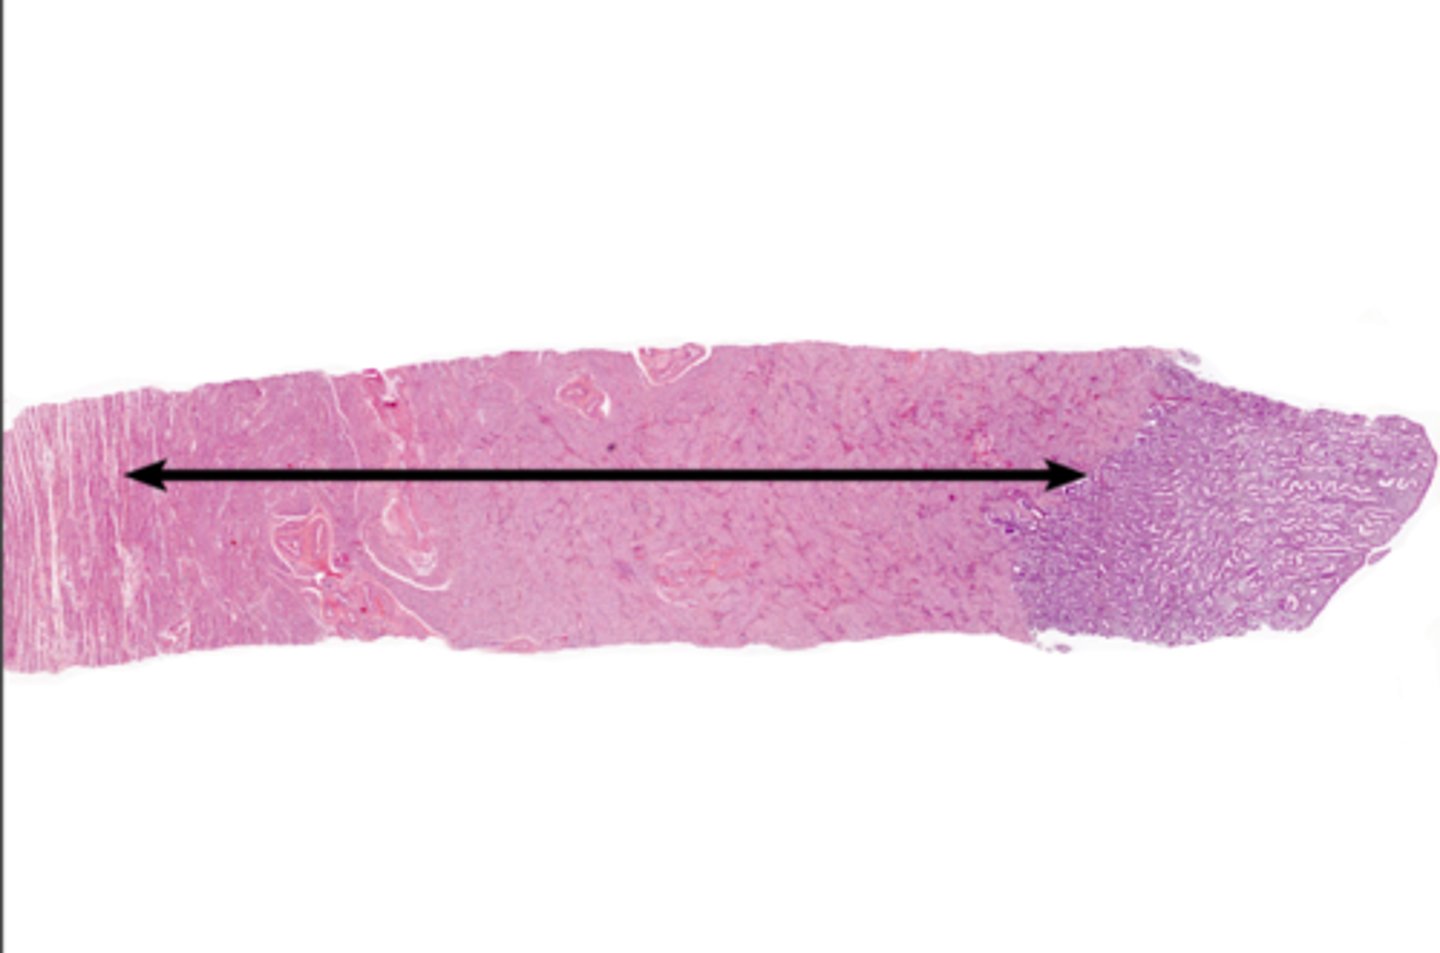

Endometrium

Endometrium

proliferate functional layer

secretory functional layer

menstrual functional layer

proliferate basal layer

secretory basal layer

menstrual basal layer

Uterine gland

Myometrium

Myometrium